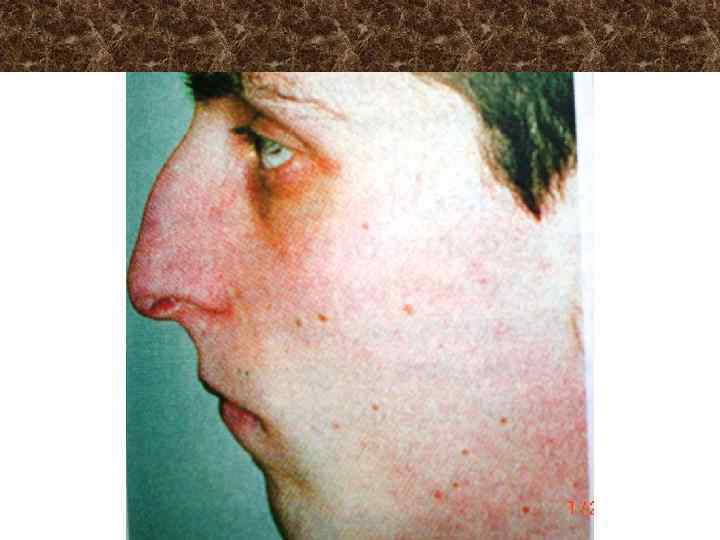

Синдром Крузона disostosis cranio - facialis ü ü Гидроцефалия Недоразвитие верхней челюсти Нос попугая Недоразвитие наружного слухового прохода и среднего уха ü Синдактилия